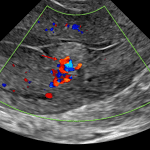

Age: 21

Sex: Female

Indication: Persistent bloody discharge 3 weeks following vaginal delivery

Findings

- Well demarcated echogenic mass in the lower endometrial canal measuring 2.2 x 1.4 x 1 cm with avid Doppler flow extending from the posterior uterine wall into this mass

- Normal appearance of the ovaries

- Trace free fluid in the cul-de-sac

Diagnosis

Retained products of conception

Well demarcated echogenic mass in the lower endometrial canal measuring 2.2 x 1.4 x 1 cm with avid Doppler flow extending from the posterior uterine wall into this mass, which in this patient with recent history of vaginal delivery is concerning for retained products of conception.

Normal appearance of the ovaries.

Trace free fluid in the cul-de-sac.